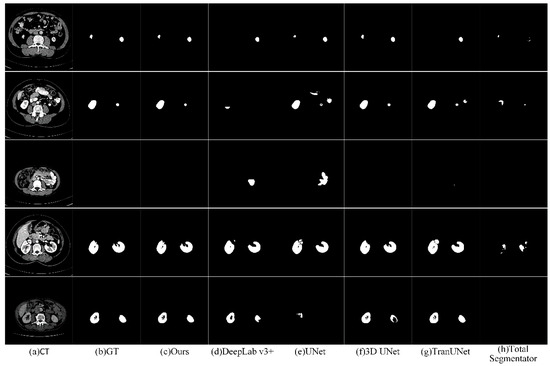

Figure 17 presents the visual comparison of the segmentation results between the proposed approach and some deep learning-based ones. It is evident from the figure that the performance of TotalSegmentator is relatively lower. While it shows strong performance on general datasets, our experiments indicate potential degradation on datasets not specifically tailored to its training. Other models exhibit varying degrees of over- or under-segmentation. Among these models, 3D UNet performs admirably by leveraging three-dimensional kidney features, although it shows limitations in delayed segmentation results. Our proposed method demonstrates strong capability in segmenting kidneys with varying locations, shapes, and sizes. The segmentation results produced by our method are much closer to the ground truth (GT) compared to those obtained by other networks.

Figure 17. Visualization results with some deep learning methods.